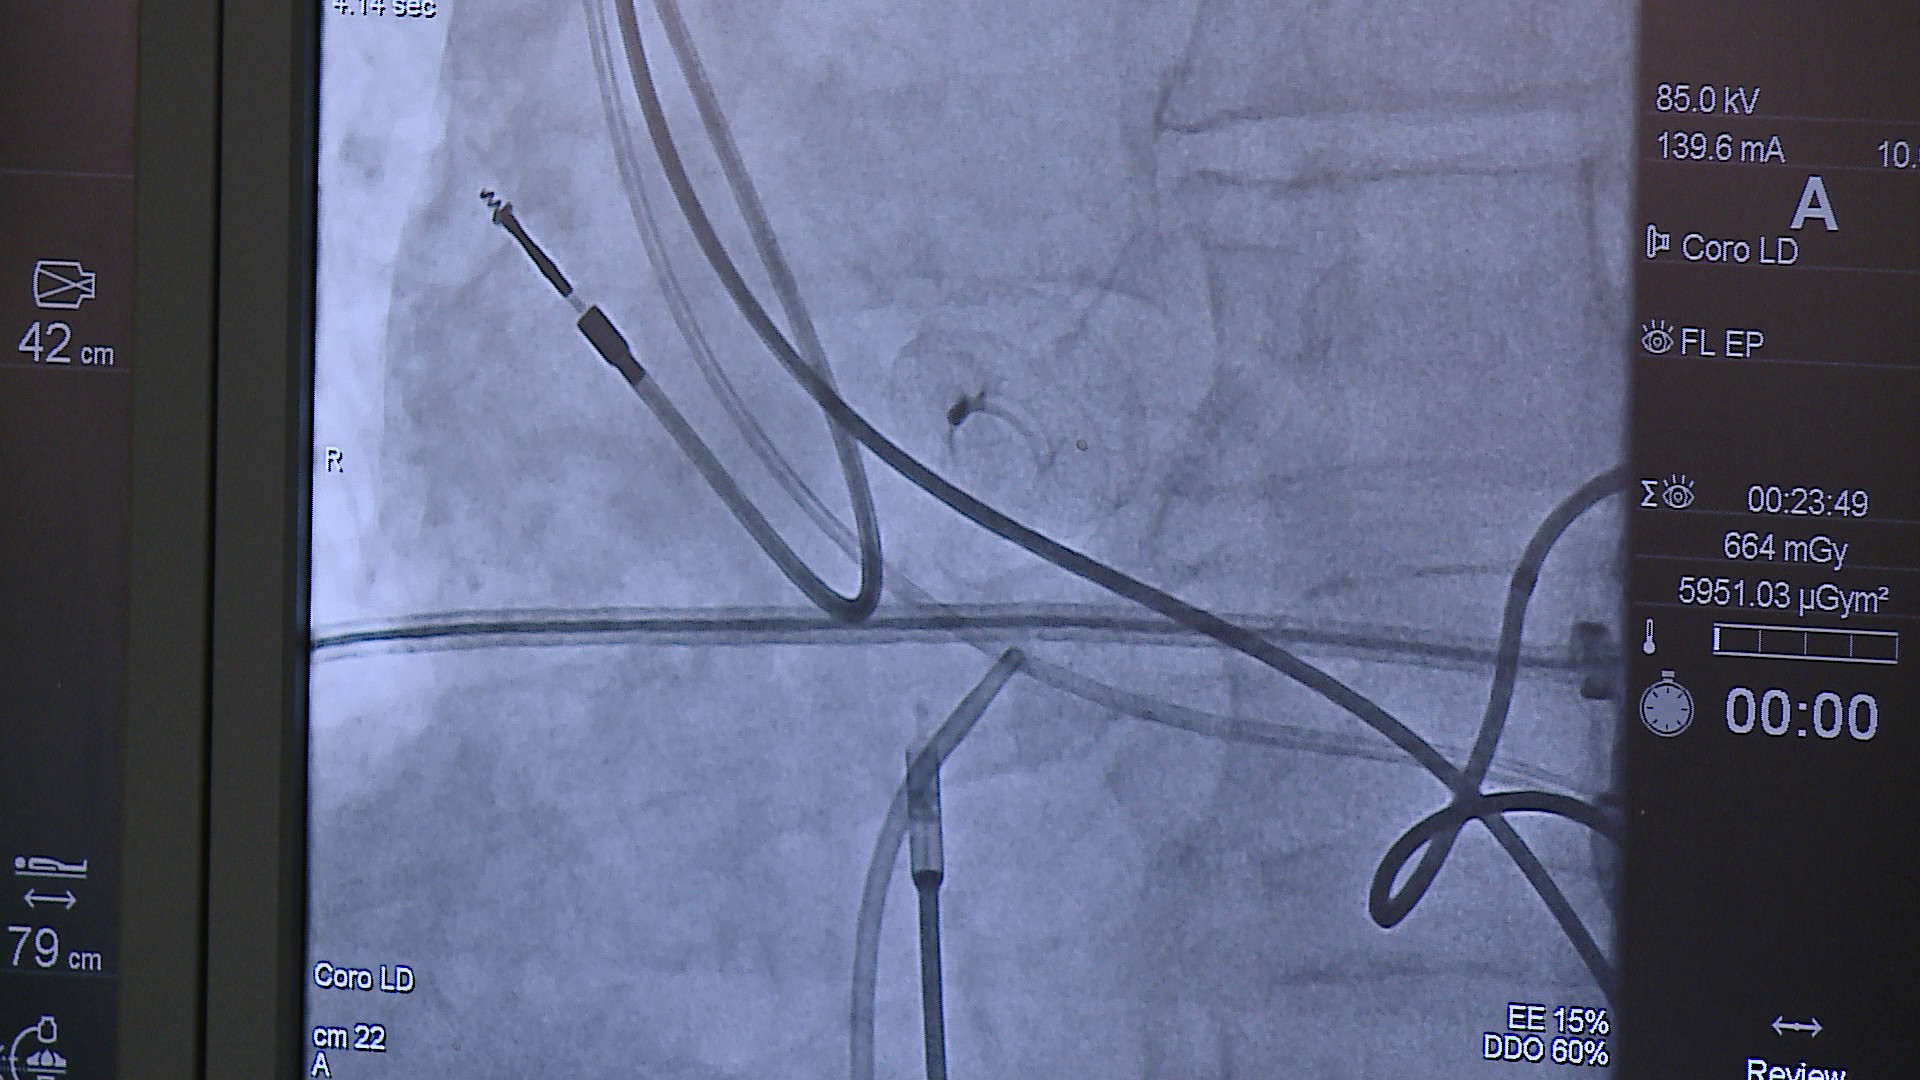

To trzeba wyraźnie podkreślić – zabieg wszczepienia przedsionkowego regulatora przepływu (AFR) u chorych z niewydolnością serca może oznaczać uratowanie im życia. Problem w tym, że na całym świecie dotąd wykonano zaledwie kilkanaście tego typu procedur medycznych, w tym jedynie cztery w Polsce. Lekarze z wejherowskiego szpitala mają być pod tym względem światowymi pionierami. Dlaczego ten zabieg jest tak bardzo ważny?

– Regulator przepływu umożliwia dekompresję obciążonego lewego przedsionka i redukcję ciśnienia napełniania lewej komory serca, co z kolei prowadzi do zmniejszenia objawów niewydolności serca – tłumaczy dr n. med. Łukasz Lewicki, kierownik Pracowni Kardiologii Inwazyjnej Szpitala Specjalistycznego im. F. Ceynowy w Wejherowie.

Operacja jest szansą dla chorych ze schyłkową niewydolnością serca, którzy dotąd mogli liczyć na poprawę stanu zdrowia jedynie po przeszczepieniu narządu, ponieważ inne metody terapii okazywały się nieskuteczne. Pierwszy na świecie zabieg wszczepienia AFR wykonali gdańscy lekarze z Uniwersyteckiego Centrum Klinicznego w 2019 roku u 11-letniej dziewczynki, o czym informowaliśmy tutaj. To stało się inspiracją dla wejherowskich kardiologów i otworzyło im pole do działania. Lekarze z Wejherowa postanowili zastosować tę procedurę medyczną u dorosłych pacjentów.

Dotąd cztery implanty wszczepiono chorym w Gdańsku, Krakowie i Poznaniu. W ubiegły poniedziałek (20 stycznia) zabieg ten przeszło trzech wejherowskich pacjentów. Operował zespół w składzie: Łukasz Lewicki, Maciej Karwowski, Sebastian Liedtke, Wojciech Piotrowicz. Asystowały pielęgniarki: Grażyna Milewska, Bożena Wojtas, Ewa Kurek oraz technicy: Anna Kaczmarek i Kamil Grzela.